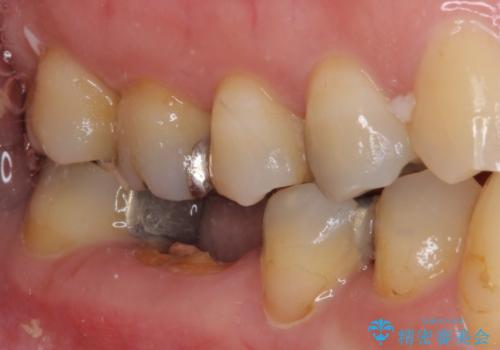

- 他院で、抜歯してインプラント補綴するしかないとのことで来院された患者様です。

診査したところ、抜歯と診断された歯は、他院での診断通り抜歯が必要でした。

ただし、インプラント以外にブリッジでの補綴治療も可能であったので、抜歯後に治癒を待って、フルジルコニアブリッジにて補綴することとしました。